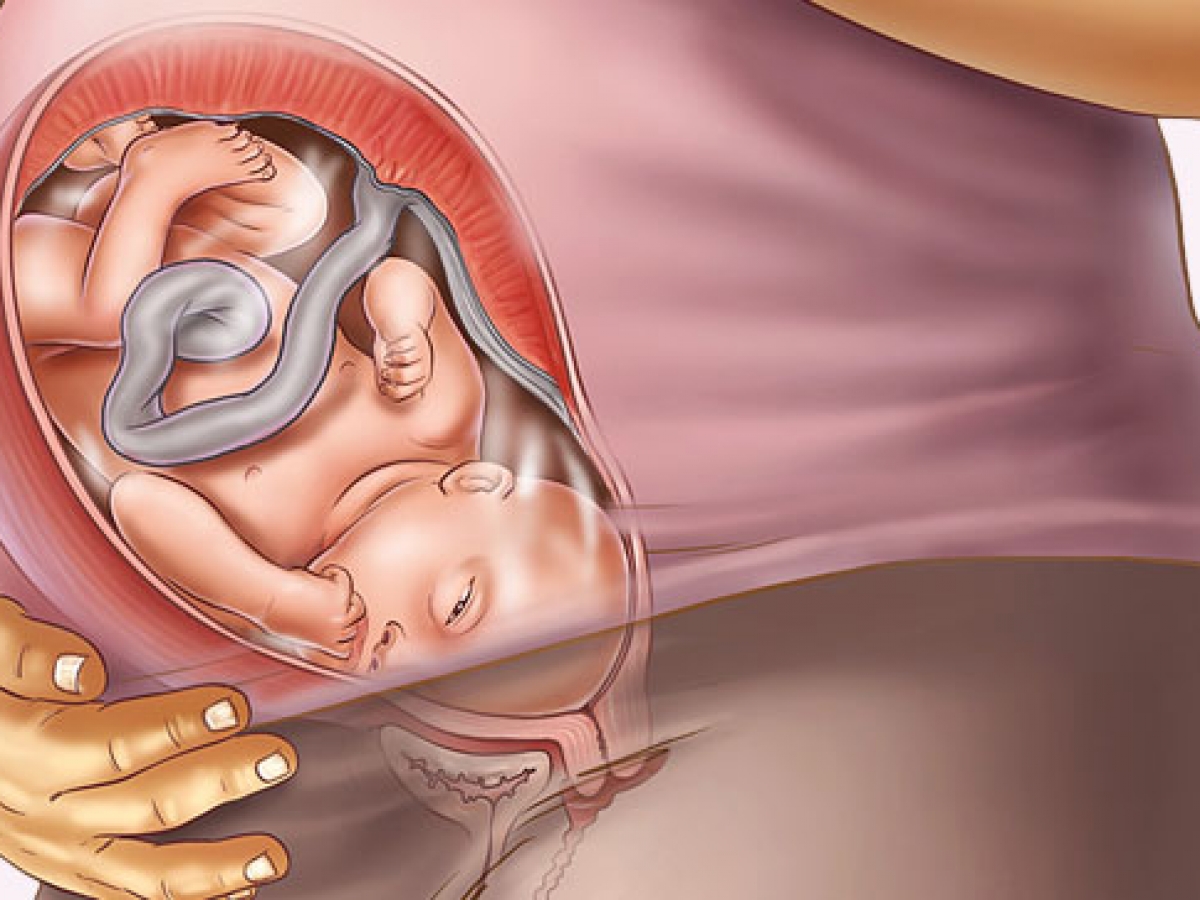

Многоводие при беременности: симптомы и лечение